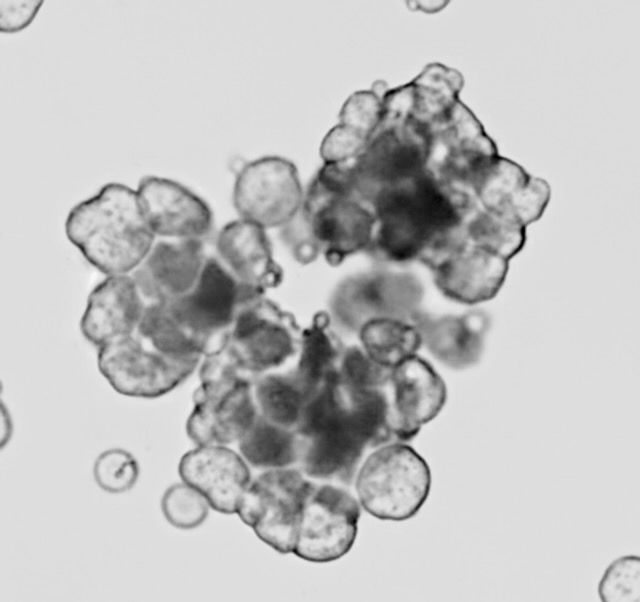

To close the gap in patient-specific, real-time monitoring, we use patient-derived tumoroid models. These living systems, grown directly from patient tumor samples, allow us to observe cancer evolution as it happens and uncover mechanisms of treatment resistance.